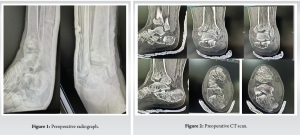

A 33 year old male came with alleged history of fall from electric pole after suffering electric shock and was taken to outside hospital and there he was diagnosed to have compression fracture of L2 (burst type) with right pilon fracture and right calcaneum fracture (sanders type 4) (Fig. 1) and later patient shifted to Apollo hospital neurologically Right hip ⅕ knee ⅕ and ankle 0/5, Left hip 1/5knee ⅕ and ankle 0/5, Perianal sensation decreased. A CT scan was done, suggestive of a displaced fracture medial malleolus and an intra-articular displaced calcaneum fracture (Figs. 2 and 3). Fracture was temporarily stabilized with below knee pop-back slab and limb elevation given. Patient underwent D12–L4 stabilization with dural repair for L2 burst fracture and cauda equina (Fig. 4). For 5 days, patient was optimized in ICU. The patient was planned for definitive fixation of calcaneal and pilon fracture.